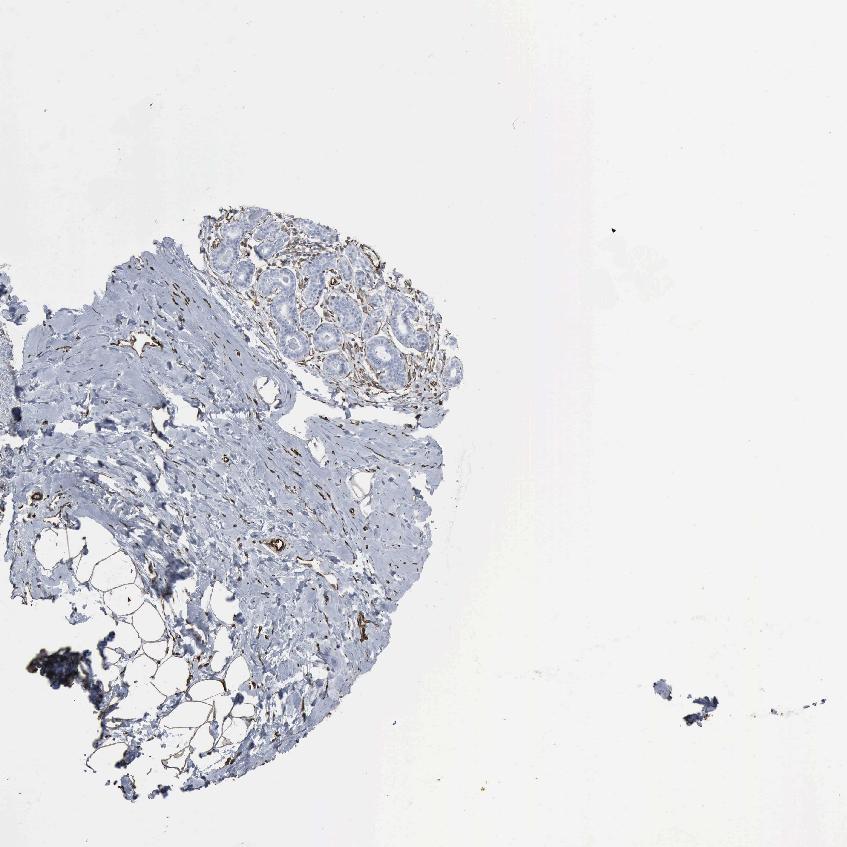

BREAST - Antibody stainingi

Antibody staining in the annotated cell types in the current human tissue is reported as not detected, low, medium, or high, based on conventional immunohistochemistry profiling in selected tissues. This score is based on the combination of the staining intensity and fraction of stained cells.

Each image is clickable and will lead to virtual microscopy that enables deeper exploration of all samples and also displays staining intensity scores, fraction scores and subcellular localization as well as patient and tissue information for each sample.

Antibody HPA018169Antibody CAB000308Antibody CAB016682

Adipocytes Not detectedMediumNot detected

Glandular cells LowNot detectedNot detected

Myoepithelial cells Not detectedNot detectedNot detected